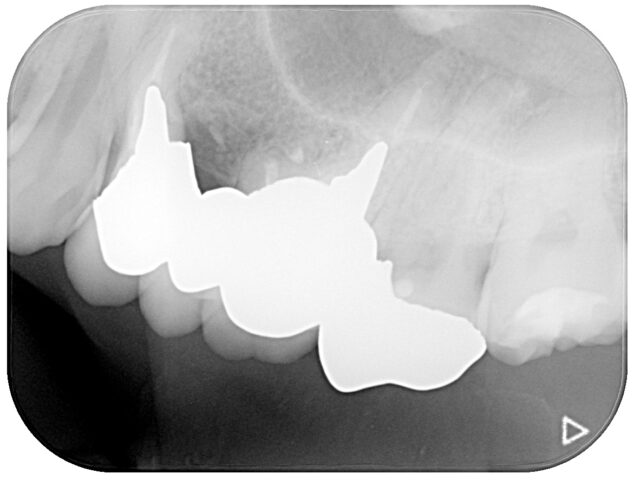

年齢 20代 性別 男性 主訴 今回の患者さんは、もともと定期検診にしっかりと通われていた意識の高い方でしたが、転勤に伴い当院へ初めて来院されました。「右上の歯が染みる」という症状があり、お口の中を拝見すると、一見しただけでは非常に小さな虫歯にしか見えません。

しかし、レントゲン検査を行うと、表面の小さな入り口とは裏腹に、内部で大きな空洞のように虫歯が広がっている像が確認されました。

患者さんには「見た目以上に虫歯が深く、治療の過程で神経に近くなる可能性があること」を事前に詳しくご説明し、可能な限り神経を残す方針で治療を開始しました治療 慎重に歯を削り進めていくと(Before/After写真参照)、やはり内部のカリエス(虫歯)は深く、神経のすぐ近くまで達していました。

通常の治療であれば神経を取る「抜髄(ばつずい)」を選択するケースも多い大きさでしたが、歯の寿命を延ばすためには神経の保存が不可欠です。そこで今回は、VPT(Vital Pulp Therapy:歯髄温存療法)を行いました。

精密な除去: マイクロスコープ(歯科用顕微鏡)を使用し、健康な組織を削りすぎないよう、感染部位のみを徹底的に除去。

MTAセメントによる封鎖: 生体親和性が高く、殺菌性・封鎖性に優れた「MTAセメント」を用いて神経を保護し、再感染を防ぐ処置を施しました。料金 4万円+税 備考 備考

本症例におけるVPTの適応および術式は、日本歯科保存学会のガイドライン、ならびに最新の臨床的エビデンスに基づき慎重に判断しています。

適応の判断: 術前の症状(自発痛の有無)やレントゲン診断、および術中の神経の露出状態や出血のコントロール具合を確認し、保存可能と診断したケースにのみ適用します。

リスクと経過観察: 処置後、一時的に痛みや違和感が出ることがありますが、経過観察を行い、神経の活性が維持されているかを定期的にチェックする必要があります。